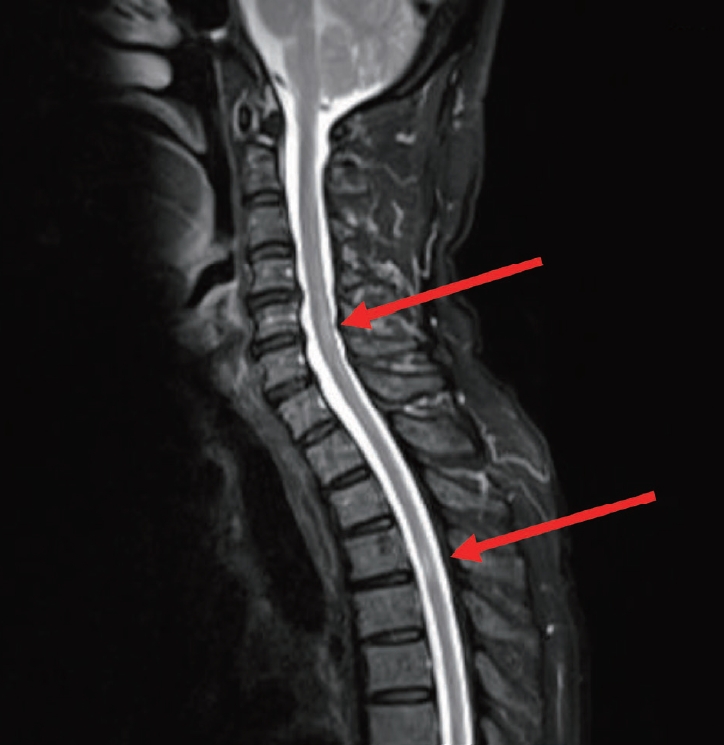

Aspergillus antigen test and (1-3)-β-D-glucan test result showed a positive result. Voriconazole 240 mg (intravenous) was applied twice a day for a month. After using antifungal agent, a result was changed to negative. Orbital invasion was observed in the MRI findings with visual disturbance, but not prominently found mucosa invasion in the cytological biopsy. So, An additional Anti-AQP4 immunoglobulin G (IgG) test for optic neuritis was done and its result was positive. The indication for additional Anti-AQP4 IgG test is that patient has optic neuritis, acute myelitis, area postrema syndrome (nausea, vomit, hiccups), acute brainstem syndrome, symptomatic narcolepsy or acute diencephalic syndrome with typical MRI lesions, symptomatic cerebral syndrome with typical MRI lesion. Therefore, additional brain and whole spine MRI was taken to discriminate NMOSD. Whole spine MRI revealed multifocal, separated, and abnormal intramedullary hyperintensity of spinal cord lesions (Fig. 3).

The MRI for the diagnosis of NMOSD including brain, orbits and spinal cord is essential in suspected cases and may also be useful for making an early diagnosis. The orbital MRI findings are the longitudinally optic nerve involvement associated with acute swelling and extensive enhancement, especially bilateral or extending into the optic chiasm.